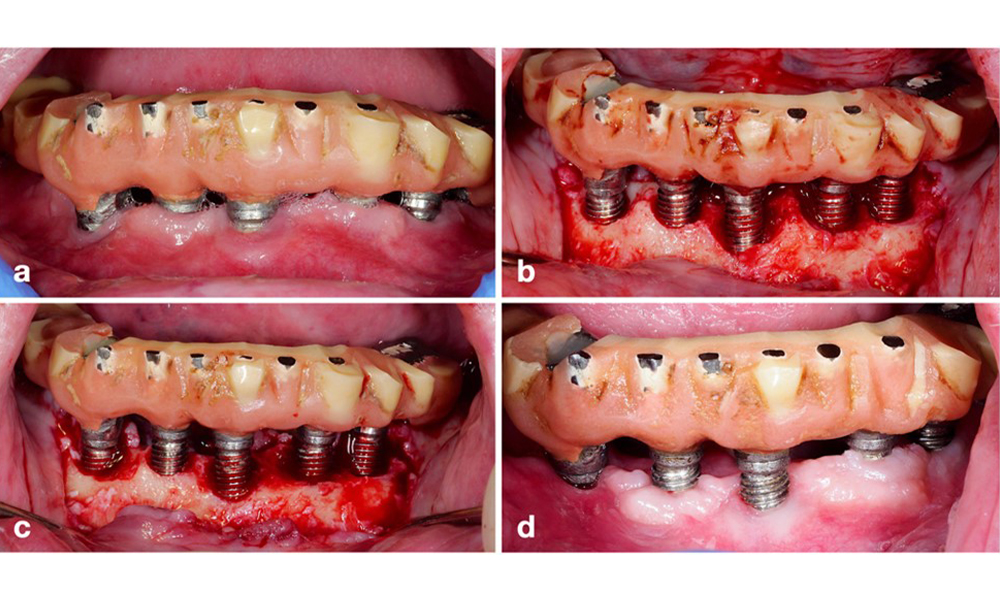

Протетичната реставрация трябва да бъде отстранена както по време на нехирургично, така и по време на хирургично лечение, за да се подобри достъпът до повърхността на импланта. Изборът на хирургична интервенция (напр. резективна, реконструктивна или комбинирана) зависи от няколко фактора: (1) морфология на дефекта (напр. хоризонтална, дехисценция, вътрекостна или комбинирана) (фигура 10), (2) повърхност на импланта ( т.е. обърната или модифицирана/"груба") и (3) наличие или липса на достатъчно кератинизирана и прикрепена лигавица.

Резективен подход (т.е. гингивектомия и/или апикално позиционирано ламбо, с/без реконтуриране на костта) трябва да се избере в случаи с предимно хоризонтална костна загуба или широки дефекти, където потенциалът за костна регенерация е ограничен (фигура 11).